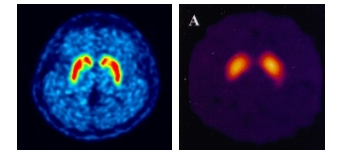

피디뷰는 퓨쳐켐의 플루오린(F-18) 표지 기술을 통해 세계 최초로 상용화한 파킨슨병 진단 신약이다.

뇌 속 도파민 운반체의 농도를 정량적으로 분석해 파킨슨병을 진단하는 원리다. 미국에선 피디뷰와 화합물이 같은 G사의 경쟁약물이 FDA 승인을 받은 상황이어서 피디뷰의 505(b)2의 승인 가능성이 높이 점쳐지고 있다.

특히 미국은 현재 요오드(I-123) 표지 의약품이 널리 사용되고 있는데, 피디뷰는 해당 의약품 대비 가격경쟁력이 높고 빠르게 영상을 취득할 수 있다. 또 경쟁사의 SPECT-CT 방식 대신 PET-CT 방식을 채택해 영상 퀄리티가 높은 것도 장점이라고 회사는 설명했다.